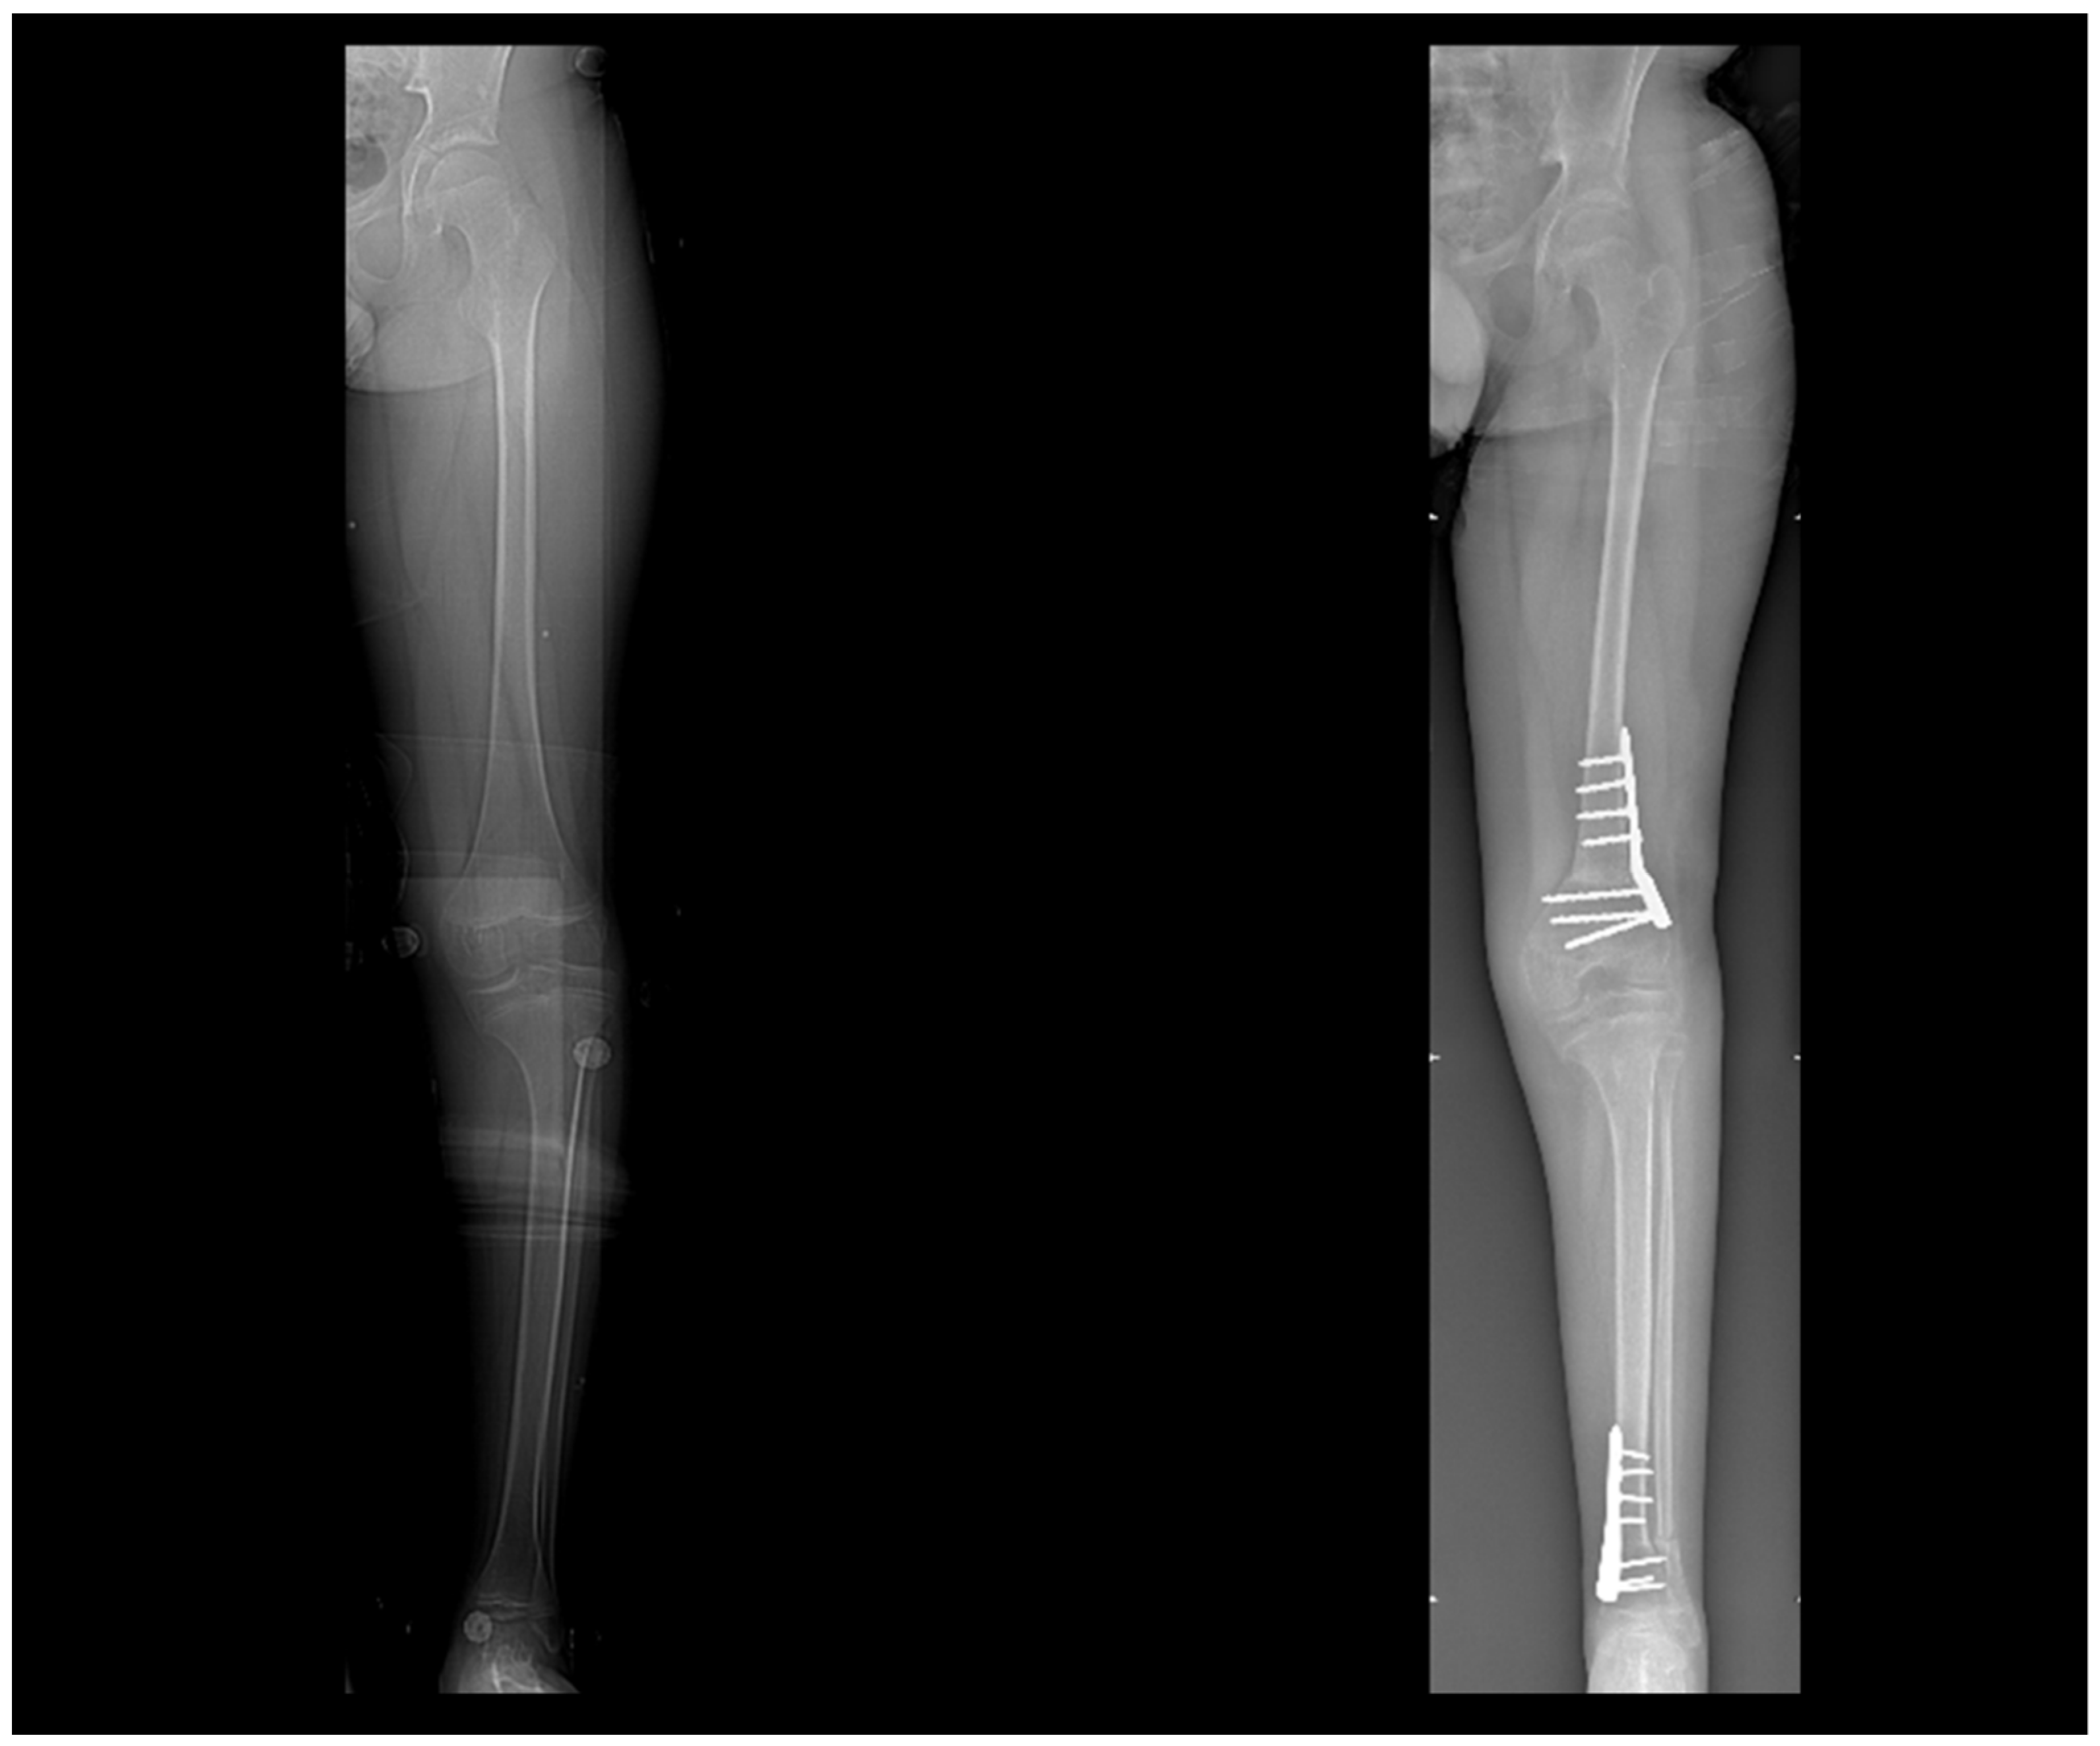

3.4. Virtual Surgical Simulation